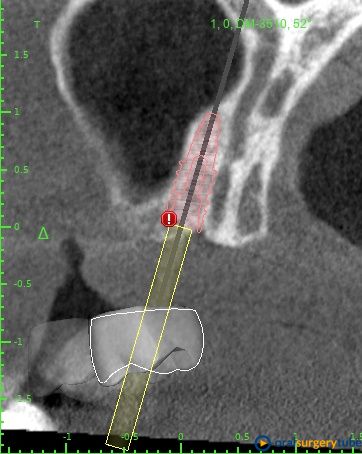

Mi plan A sería: Jugando con la cirugía guiada me cabría un implante mesial de 4x8,5 y uno pterigoideo de 3,5x10, éste en hueso nativo 100% pero con la anatomía justita. Tengo dudas si jugar en ambos lechos usar las fresas Versha para ganar algo más de altura en el mesial y mejor condensación del lecho en ambos... O no liarla y dejarlo así como os digo sin versha.